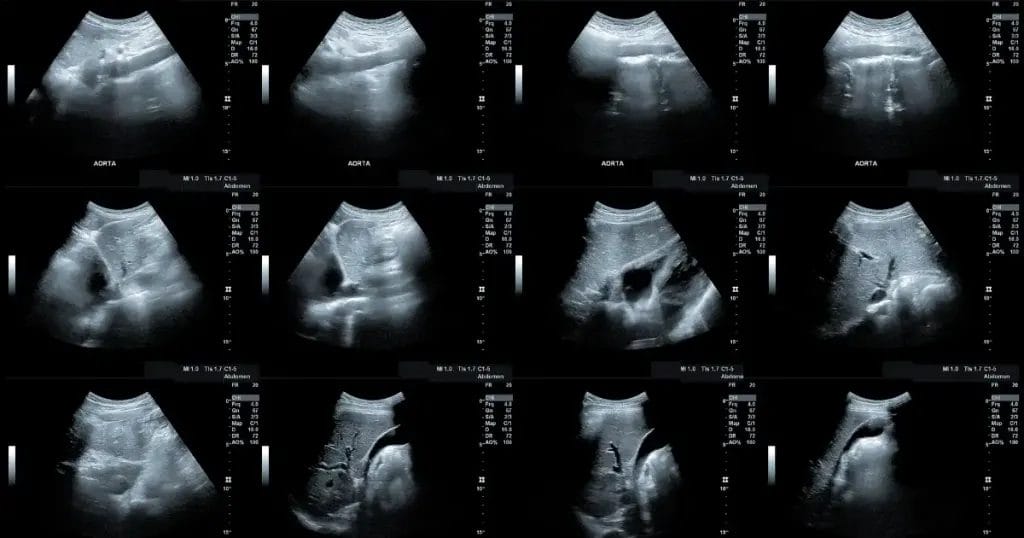

تشمل أعراض انفجار الشريان الأورطي البطني ما يلي:

- ألم عميق ومستمر في أسفل الظهر أو البطن.

- ألم في الساق أو الفخذ أو منطقة الحوض.

- شعور بنبض في البطن يشبه دقات القلب.

- ضيق في التنفس.

- تسارع في ضربات القلب.

- انخفاض ضغط الدم.

- دوار أو إغماء.

- غثيان أو قيء.

- تعرق ورطوبة في الجلد.